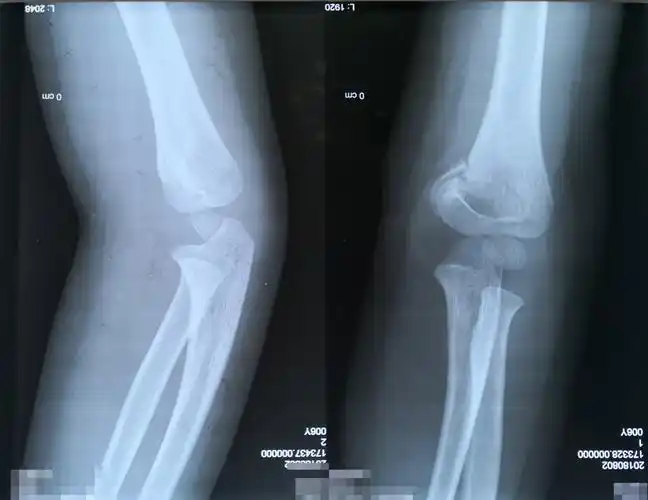

9岁儿童肘部肱骨骨折,请看x片,需要手术治疗还是保守治疗?

【骨小雅课堂】暑期儿童意外骨折多,儿童肱骨髁上骨折怎么治疗?